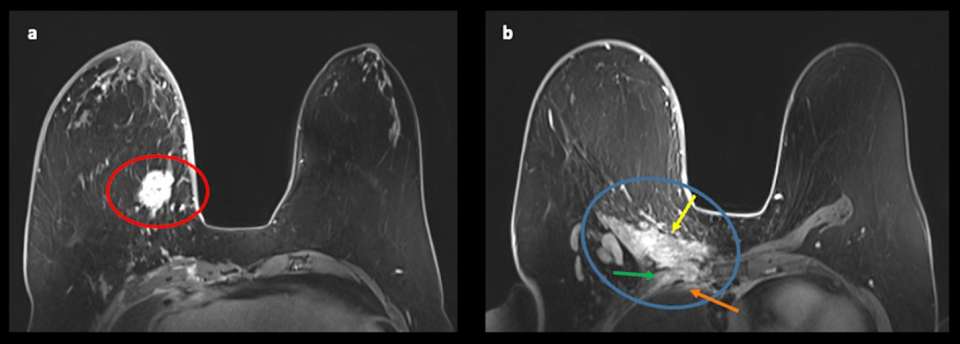

Case 1: Patient presented with a palpable right breast lump. Patient underwent diagnostic MRI which demonstrated the following (Figure 2).

This patient was diagnosed with triple negative invasive ductal carcinoma. Due to extent of disease, patient was treated with neoadjuvant chemotherapy.